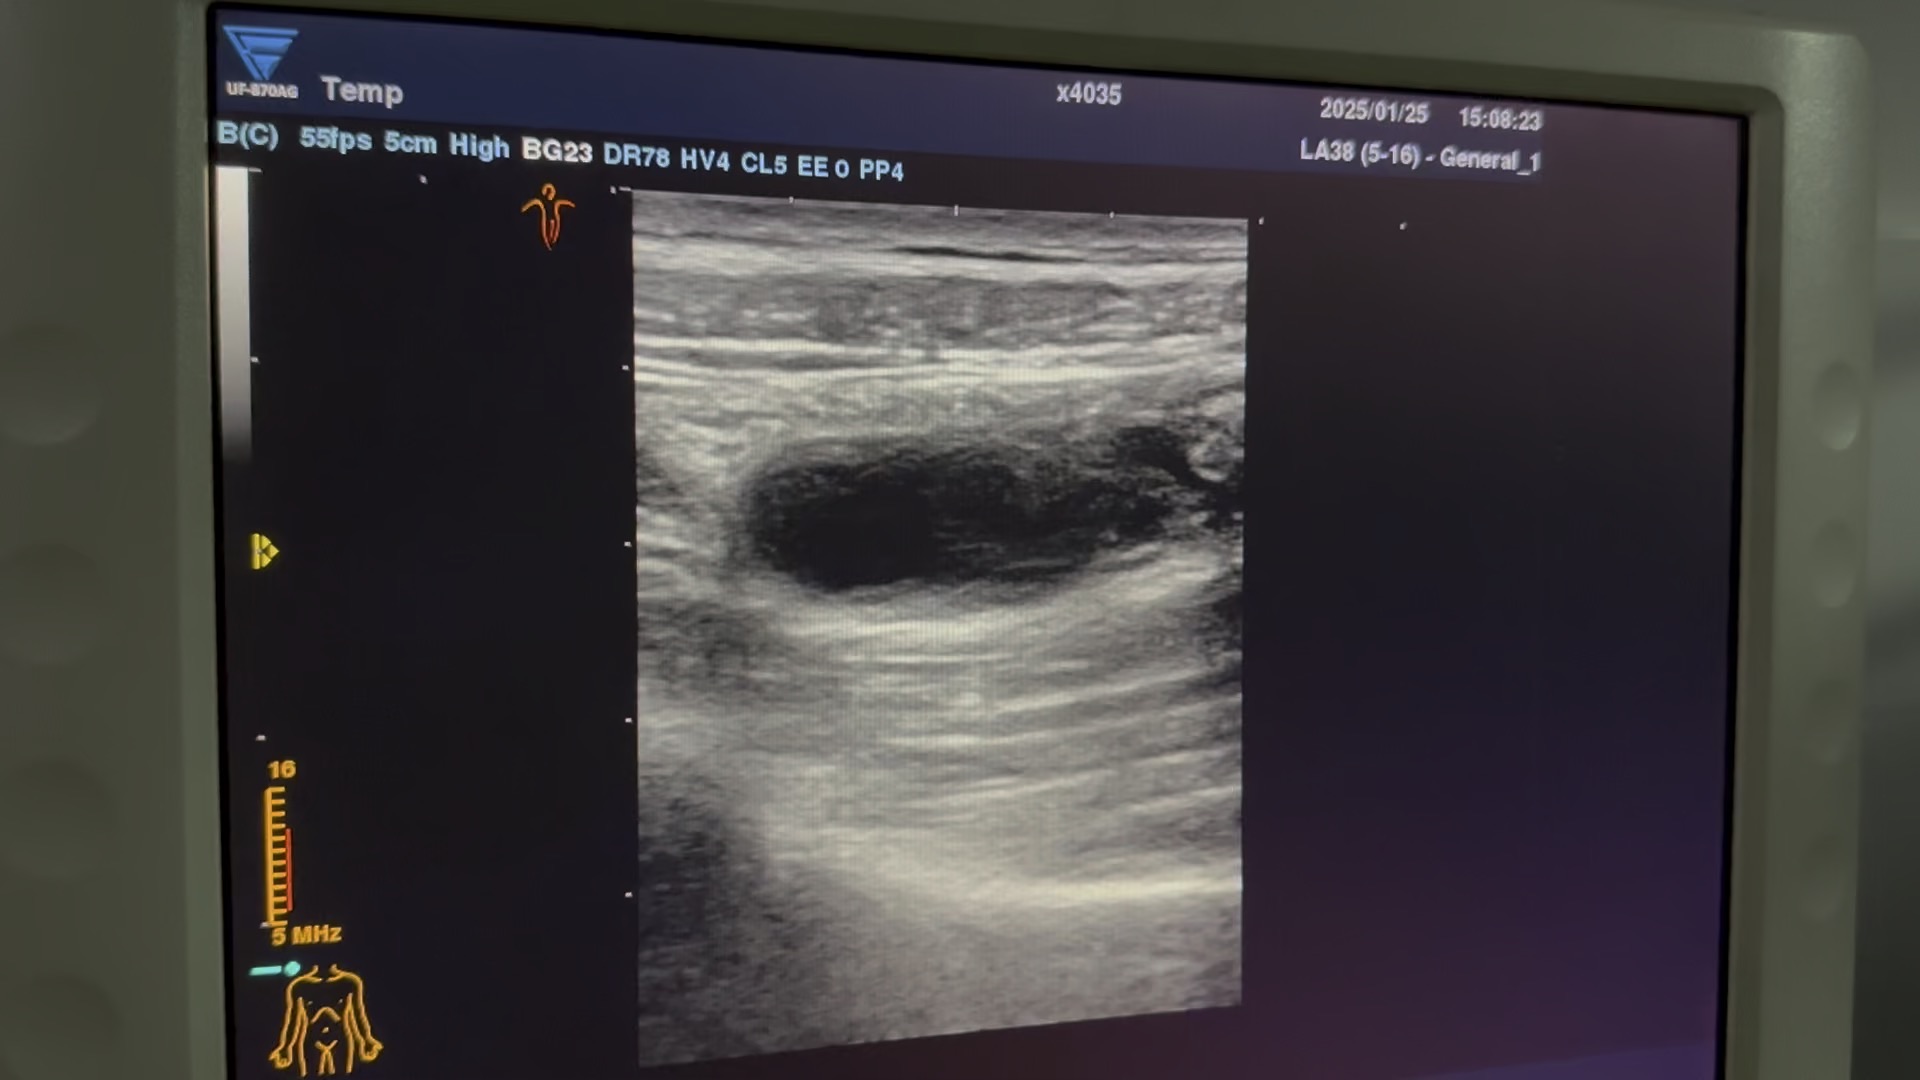

阑尾炎超声图

偶尔腹疼的阑尾炎